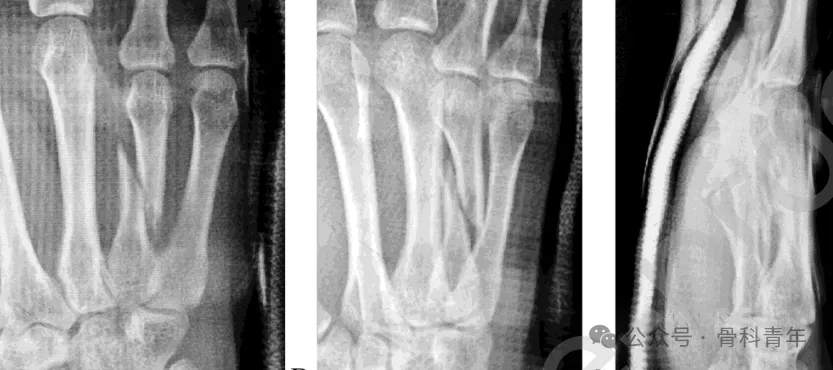

步骤1:常规消毒铺巾,尺神经阻滞麻醉。掌骨骨折通常远端移位,近端因腕掌关节及临近掌骨的存在,位置相对固定。先将一枚1.5mm克氏针经第5掌骨穿入第4掌骨骨折近端,将骨折近端固定。

步骤2:掌指关节屈曲90°,经掌骨远端关节面置入一枚1.5mm克氏针,穿入远端骨块髓内。后牵引环指、挤压骨折断端闭合复位,如复位困难,可采用克氏针经皮撬拨或将克氏针折弯后辅助复位(如下图)。

步骤3:复位后,将远端髓内克氏针直接穿入近端骨块髓腔,临时维持复位。在位置满意后,经第5掌骨置入2枚克氏针至远端骨块,再置入一枚固定近端。在远近端各固定2枚后,去除髓内固定克氏针。固定后克氏针留置皮外,可回归工作。